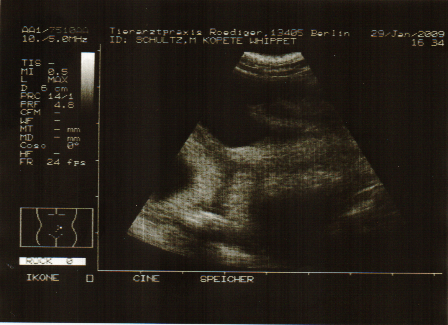

Die Neugier war zu groß und deshalb haben wir nun doch eine Ultraschalluntersuchung machen lassen.

Wir waren gestern in der Sonntagssprechstunde bei unserer netten Tierärztin, die uns zu unserer großen Freude drei sich munter bewegende Embryonen zeigen konnte.

Da man beim Ultraschall die richtige Anzahl der Fruchtanlagen nicht genau bestimmen kann, können wir gemäß der Erfahrungswerte aber auf jeden Fall so in etwa mit fünf bis sechs Welpen rechnen.

Für Kopete verlief die Untersuchung, die im Stehen durchgeführt wurde, völlig ohne Stress.

Kopetes Ultraschalluntersuchung

Kopete 5 Wochen trächtig